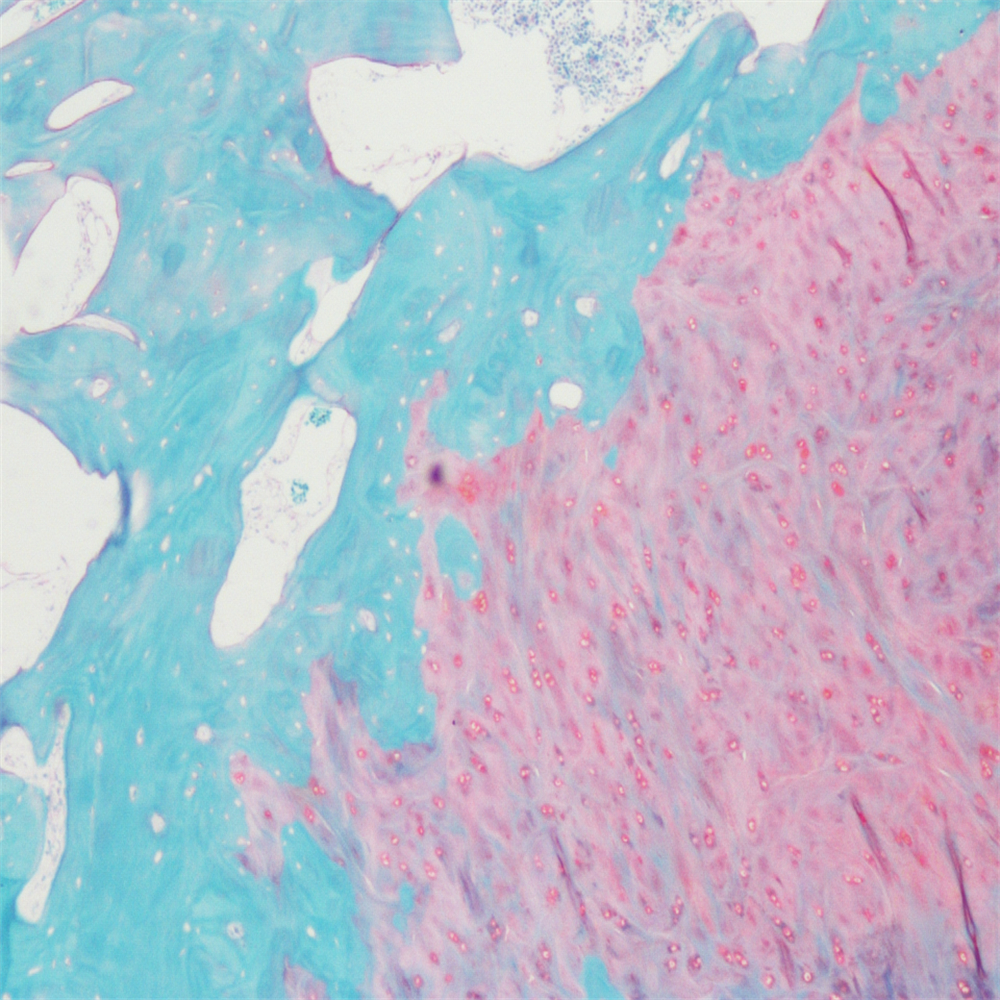

番红-固绿染色(软骨)在涉及关节软骨及软骨下骨的形态学研究中,常需联合使用多种染料以显示其组织学结构。其中,起源于上世纪60年代的番红O(safranin O)-固绿(fast green)染色因可以直观反映关节软骨、软骨下骨和骨组织的结构而备受青睐。软骨呈红色,成骨呈绿色。

番红-固绿(软骨)染色法的染色原理在于嗜碱性的软骨和碱性染料番红O结合呈现红色,嗜酸性的骨和酸性染料固绿结合而成绿色或者蓝色,与呈现红色的软骨对比鲜明,从而将软骨组织和骨组织区分开。番红O是一种结合多阴离子的阳离子染料,其显示软骨组织是基于阳离子染料与多糖中阴离子基团(硫酸软骨素或硫酸角质素)结合。番红O着色与阴离子的浓度近似成正比关系,间接反映基质中蛋白多糖的含量和分布。当软骨收到损伤时,软骨中的糖蛋白会释放出来,使基质成分分布不均匀,从而导致番红O淡染或不着色。通过图像分析软件可以对番红O染色的软骨基质进行定量分析。固绿与胶原纤维结合,不宜褪色。

实验结果展示:

番红固绿-骨>